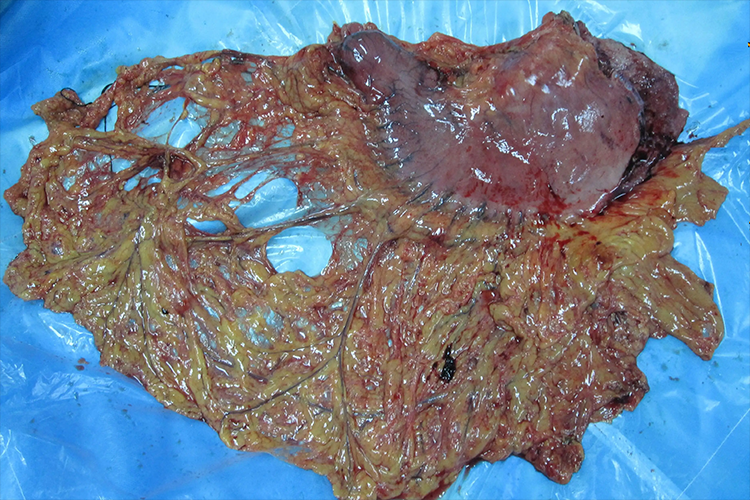

胃癌的治疗策略是以外科手术为主要方式的综合治疗。部分早期胃癌可内镜下切除,进展期胃癌强调足够的胃切除和淋巴结清扫术。化学治疗适用于不可切除或术后复发的患者,也可用于胃癌根治术后的辅助治疗。